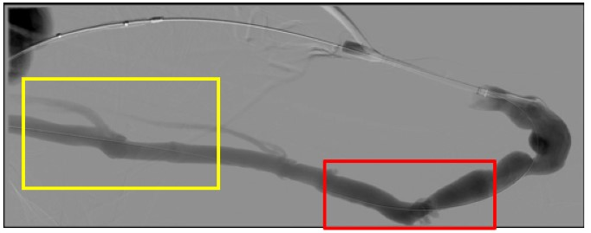

AVG动脉端走行设计不良致血栓反复发生

女性,40岁,SLE,CKD5,因桡动脉闭塞左前臂RC-AVF改建左肱动脉(肘上)-腕部头静脉间置

AVG 1月,短期内无诱因血栓形成2次